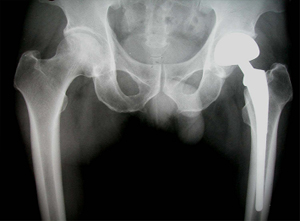

• 고관절 치환술 후 X-선 고관절 치환술 후 X-선 사진

상기 환자는 46년 전부터 고관절 통증이 있었으며, 12년전 Lt. total hip replacement(THR)을 받은 분으로 2년 전부터 통증으로 인해 물리치료를 받았지만 통증이 지속되었고, 본원 OS 외래에서 방사선 촬영하여 Lt. THR loosening 소견으로 revision O.P. 위해 입원하여 O.P.이후 재활위해 물리치료실로 의뢰됨